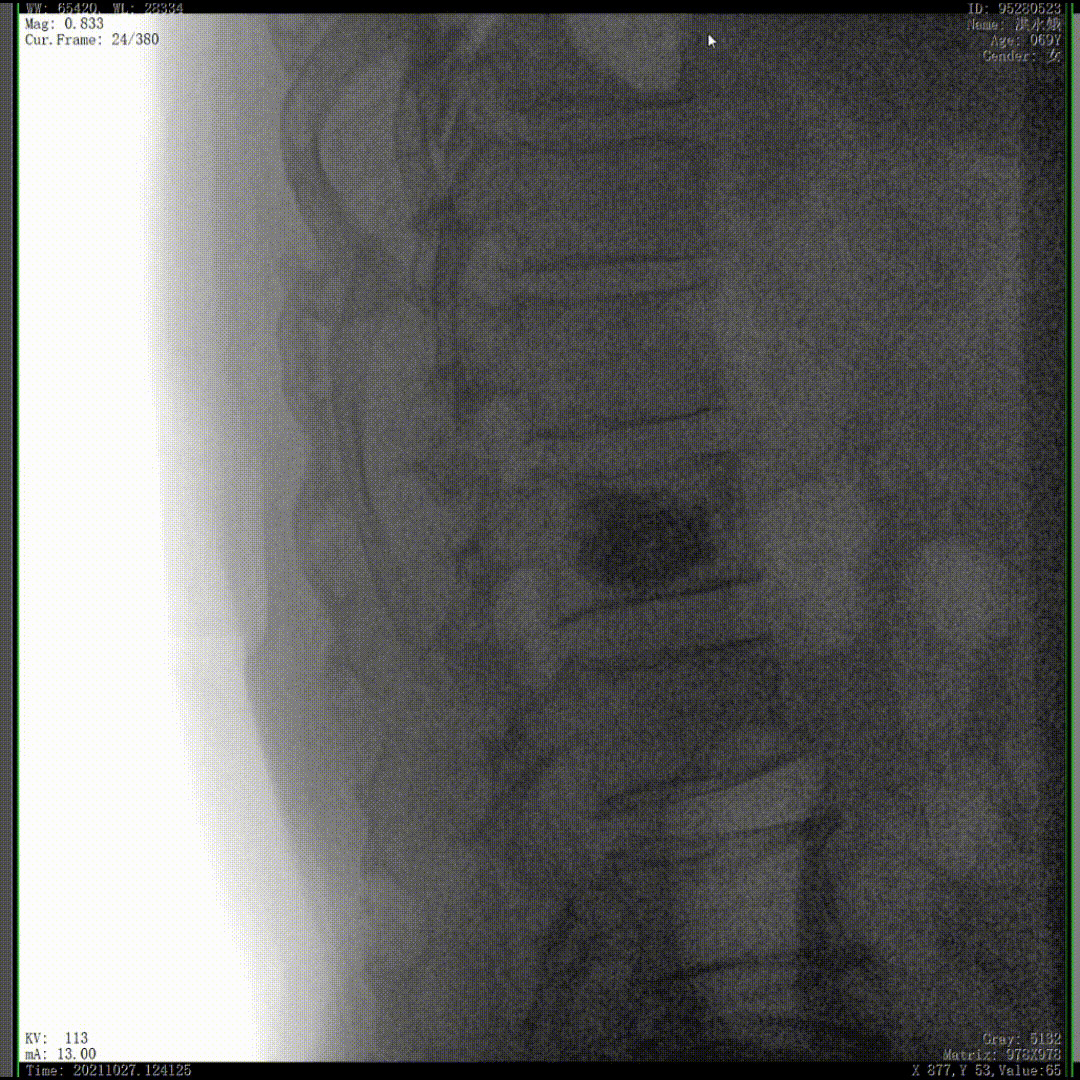

我們完成了椎體成形術(shù)以后,在二維的正側(cè)位影像上還不能看清骨水泥的滲漏情況,通過(guò)三維影像就可以360°的觀察骨水泥在椎體里到底是怎么彌散的。如果當(dāng)時(shí)我們判斷出來(lái)質(zhì)量不好,可能還需要進(jìn)行翻修,這是在二維影像上不能看到的。